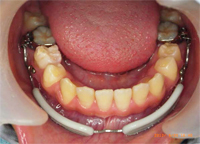

リップバンパーとは

リップバンパーは、下顎に使用される機能的矯正装置の一つです。口唇の機能圧を排除または利用することで、下顎前歯の唇側移動、永久歯の萌出スペースの獲得、反対咬合の改善を目指します。